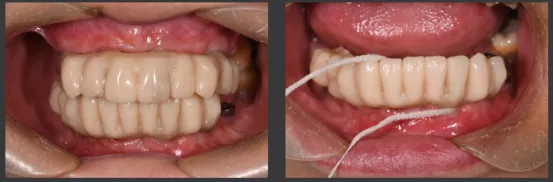

· 口内pick-up 固定临时修复体,患者上下颌咬合关系良好。

即刻修复后患者的正侧貌美学评估:

正貌美学评估:

· 面部对称、三等分,面中线与中切牙中线一致,上下唇可自然闭合。

· 侧貌美学评估:

· 上唇丰满度:适中,鼻唇角105°,上下唇位于美学E线,直面型。

· 预告面型及修复后与修复前对比,患者的正侧貌美学得到了极大的改善,凸面型变为直面型。